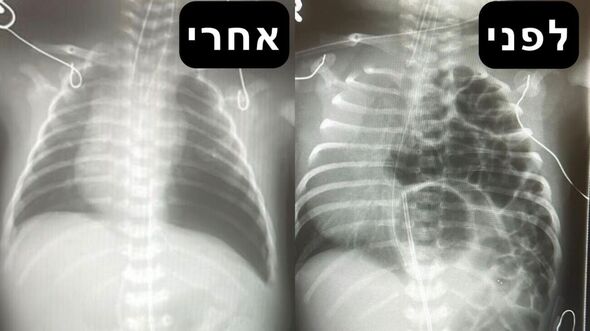

צילום מתוך דף הפייסבוק מרכז שניידר לרפואת ילדים בישראל

בצילומי החזה שבוצעו לפני ההתערבות הכירורגית מודגמות לולאות מעי בתוך חלל בית החזה של התינוק. לאחר הניתוח הצליחו הצוותים לתקן את הסרעפת ולהחזיר את הקיבה, הטחול, המעי הדק והמעי הגס אל מקומם הטבעי והתקין בחלל הבטן.